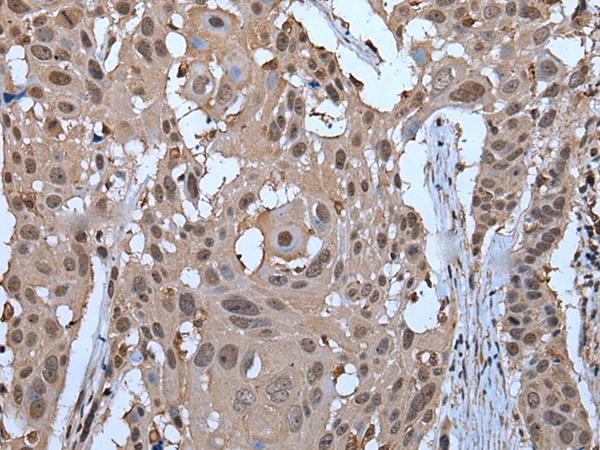

- Immunohistochemistry of paraffin-embedded Human colorectal cancer tissue using ZNF787 Polyclonal Antibody at dilution of 1:45(×200)

- Immunohistochemistry of paraffin-embedded Human esophagus cancer tissue using ZNF787 Polyclonal Antibody at dilution of 1:45(×200)